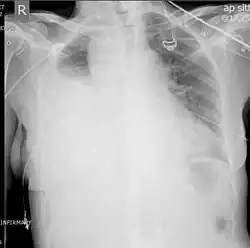

Chest X-ray showing left sided hemothorax (arrowed)

Chest X-ray

Two chest X-rays: left showing a massive left-sided hemothorax; right showing a massive right hemothorax

A chest X-ray is the most common technique used to diagnosis a hemothorax.[23] X-rays should ideally be taken in an upright position (an erect chest X-ray), but may be performed with the person lying on their back (supine) if an erect chest X-ray is not feasible. On an erect chest X-ray, a hemothorax is suggested by blunting of the costophrenic angle or partial or complete opacification of the affected half of the thorax. On a supine film the blood tends to layer in the pleural space, but can be appreciated as a haziness of one half of the thorax relative to the other.[5] A small hemothorax may be missed on a chest X-ray as several hundred milliliters of blood can be hidden by the diaphragm and abdominal viscera on an erect film. Supine X-rays are even less sensitive and as much as one liter of blood can be missed on a supine film.[24]